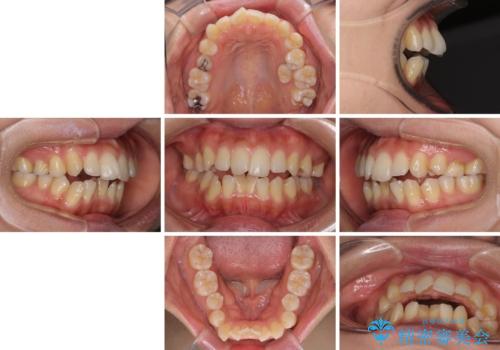

残存乳歯とオープンバイト インビザラインによる矯正治療

- 前歯のデコボコと咬み合わせを気にして来院された患者様です。

左上奥歯には乳歯が残存しており、後続永久歯は舌側に転位していました。

また、舌の突出癖の影響で上下前歯が接触していないオープンバイトとなっており、奥歯に負担のかかる咬み合わせとなっていました。